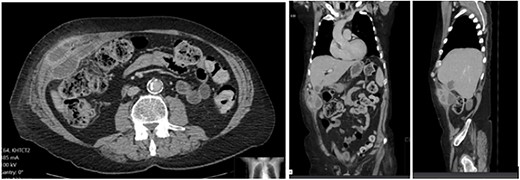

A 65-year-old gentleman with a body mass index of 29.6 and medical history of Guillain–Barré syndrome, type 2 diabetes mellitus, hypertension, and chronic pain was referred to our outpatient clinic with intermittent upper abdominal pain. His surgical history included an open appendicectomy. He was wheelchair-bound outside his home and received weekly assistance from a carer. On examination he was anicteric. His abdomen was soft, but a mildly tender mass was palpable in the right upper quadrant. An initial computed tomography (CT) scan showed thickening of the gallbladder and a collection extending from the fundus and infiltrating the anterior abdominal wall (Fig. 1). Further scans showed extension of the collection towards the midline (Fig. 2). He subsequently presented to the emergency department with purulent discharge from an external orifice adjacent to the umbilicus. An ultrasound-guided 6Fr pigtail drain was then placed into the known abdominal wall collection.

CT abdomen with portal venous contrast showing gallbladder collection extending to lateral abdominal wall.